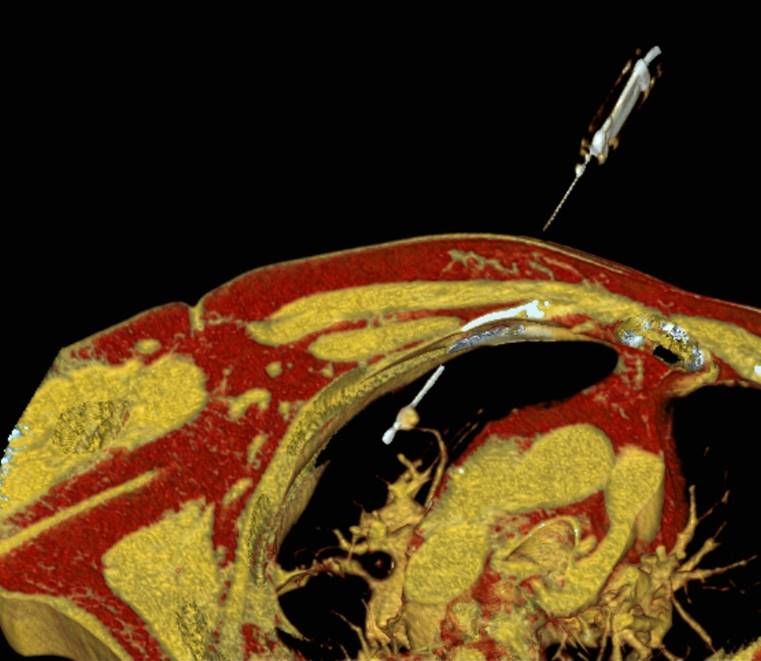

RFA zur Therapie des Osteoidosteoms

Das Osteoidosteom ist ein gutartiger, jedoch sehr schmerzhafter Knochentumor, der bevorzugt bei jüngeren Patienten auftritt. Die Radiofrequenzablation (RFA) hat sich in den letzten Jahren zu einer zuverlässigen, minimalinvasiven Therapieoption bei der Behandlung des Osteoidosteoms entwickelt und wird seit über 15 Jahren an der Uniklinik Tübingen angewandt.

Abbildung: Osteoidosteom (Pfeil) im Schienbein bei einem jungen Patienten. Unter CT-Bildgebung wird ein spezieller Applikatoren unter CT-Bildgebung in das Osteoidosteom eingebracht. Durch Hitze wird dieses effektiv und dauerhaft zerstört.